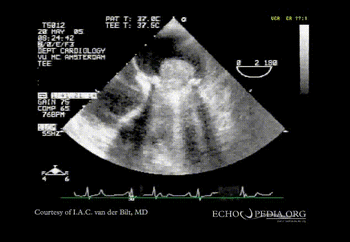

Case 2:

A 20 year old male diagnosed with mitral vale thrombus The TEE shows a giant thrombus on the mitral valve

An apical 4 chamber view of a swinging heart